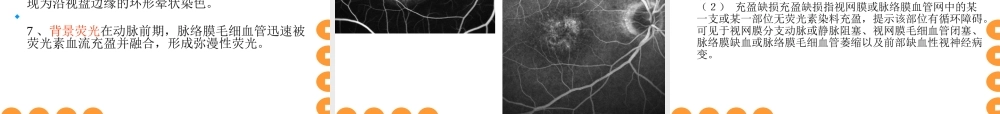

第一节荧光眼底血管造影第一节荧光眼底血管造影荧光素眼底血管造影(FFA)是当代眼科诊断眼底病常见重要的检查方法之一。对眼底病的诊断、鉴别诊断、治疗选择、预后的推断都具有重要意义。眼底荧光血管造影眼底荧光血管造影眼底荧光血管造影的原理操作方法异常荧光图象的表现。一、眼底荧光血管造影的原理一、眼底荧光血管造影的原理荧光素钠又称荧光红、荧光黄,是大量荧光物质中最富有荧光特性的化合物。其分子式C20H10O5Na2,分子量为376.27(Dalton)。在自然界,某些化合物受光线照射后,吸收辐射光的部分能量,并可发射出不同于原有波长的光线。当光线停止照射后,被照射的化合物发射的光线在9-10秒内停止者,称为荧光。用于血管造影的荧光素是一种染料,一般以钠盐的形式存在,即荧光素钠。荧光是一种电子现象,主要受波长200~800nm光线的作用。眼底荧光血管造影时,眼底血管中循行的荧光素吸收波长被490nm的蓝光激发后,发射出波长520nm的绿光。人们根据荧光素的这种吸收和发射光谱的差异作为荧光造影机滤光片选择和组合的依据。一、眼底荧光血管造影的原理一、眼底荧光血管造影的原理眼底荧光血管造影(fundusfluoresceinangiography,FFA),是将荧光素钠荧光素钠作造影剂从肘静脉注入,利用特定组合的滤光片和眼底照相机,观察并连续拍摄眼底血管中荧光素循行时吸收激光后所发射出的荧光,是主要反映视网膜血管及灌注状况的一种重要诊断技术。该技术的特点是将眼底检查从眼底镜下静态的形态学观察转变为动态的循环动力学研究,使眼底病的诊断方法由主观检查转变为可提供客观依据的科学鉴定。眼底荧光血管造影的检查结果可为临床医生提供眼底病诊断和治疗的客观指标。二、常用眼底造影系统二、常用眼底造影系统1、传统眼底照相机常用的有CANON,TOPCON,NIKON,ZEISS,KOWA等。2、激光扫描检眼镜(ScanningLaserOphthalmoscope,SLO)3、共焦激光扫描(检眼镜)系统(CSLO)共焦激光扫描(检眼镜)系统(CSLO)其中海德堡视网膜血管造影Ⅱ(HeidelbergRetinaAngiography2,HRA-Ⅱ)海德堡视网膜血管造影Ⅱ(HeidelbergRetinaAngiography2,HRA-Ⅱ)比较常用。KOWATOPCONCANON海德堡HRAHRA-ⅡHRA-Ⅱ现代眼底荧光造影使用数码图象处理系统进行血管造影的图象处理。在共焦光学系统中,用一个特定波长的激光光束激发荧光素钠造影染料,将光束聚焦于视网膜上,激光光束周期性地扫描视网膜,得到视网膜的二维图象。...